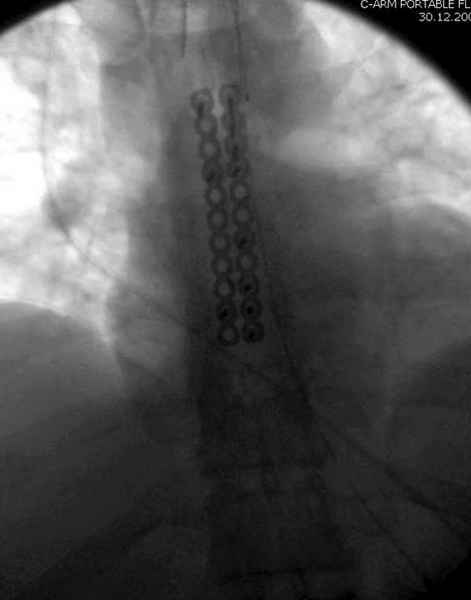

Юра, интересно, насколько такой остеосинтез контролирует степень репозиции, а то у меня имеются снимки девочки 11 лет, направленной ко мне на консультацию из одной из республик бывшего союза.

После торакальной операции, по-видимому, сильно натянули проволоку, и в результате получился захлест отломков в друг друга.

С такими продольными несращениями мне не приходилось иметь дело, поэтому направил в один из центральных институтов детской ортопедии России.

А простые посттравматические ложные суставы грудины приходилось оперировать с ограничителем сверла и с фиксацией 2.4 мм пластинами с угловой стабильностью.